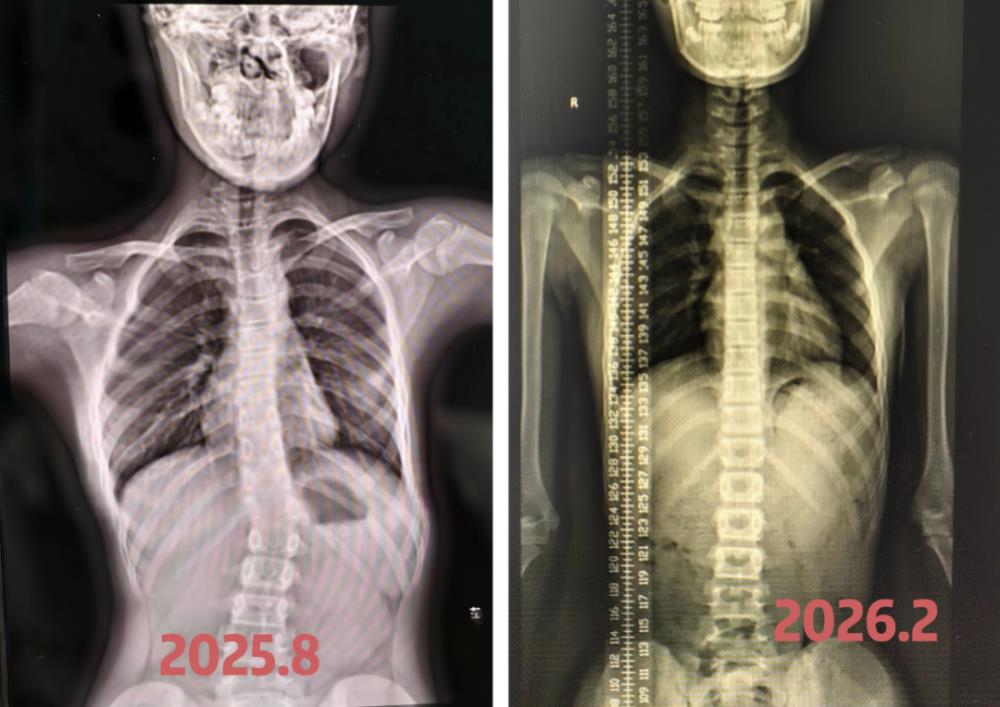

寒假伊始,两位学员主动报名本次寒假训练营,希望进一步巩固康复效果。入营前的拍片复查传来喜人消息:学员 A 的脊柱侧弯角度从 40° 下降至 27°,学员 B 的脊柱侧弯角度恢复至基本正常水平,半年的坚持与付出,终换来了实实在在的康复成果。这组亮眼的数据,不仅见证了科学训练的显著效果,更印证了孩子与家长携手坚持的珍贵意义。